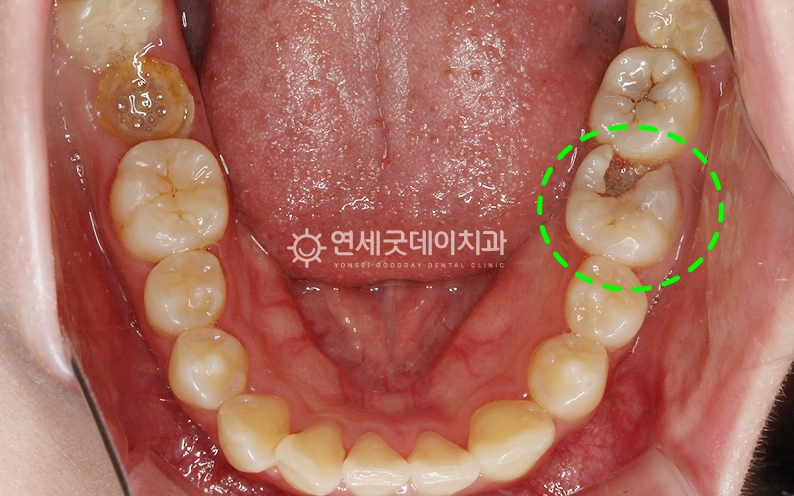

● 담당과 : 보존과 어금니 부위의 큰 충치를 주소로

#27, 36 부위에 큰 충치가 관찰되며

두 부위 모두 발치를 고려할 정도로 큰 충치였으나 또한 사진상 표시된 부위의 인접 치아는

신경치료를 통해 손상된 신경관을 제거 및 소독한 뒤 환자분은 치아 머리가 많이 손상된 상태였기 때문에

자연치아 살리기 과정 중 이후 약해진 치아를 보호하고

이어서 #27 부위도 신경치료를 진행하였으며